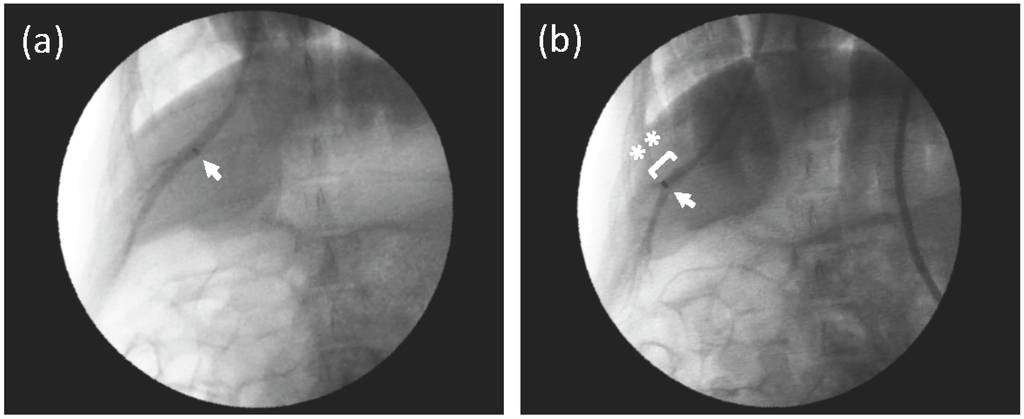

3.1. Venography of the Hepatic Vein in the Right Medial Lobe